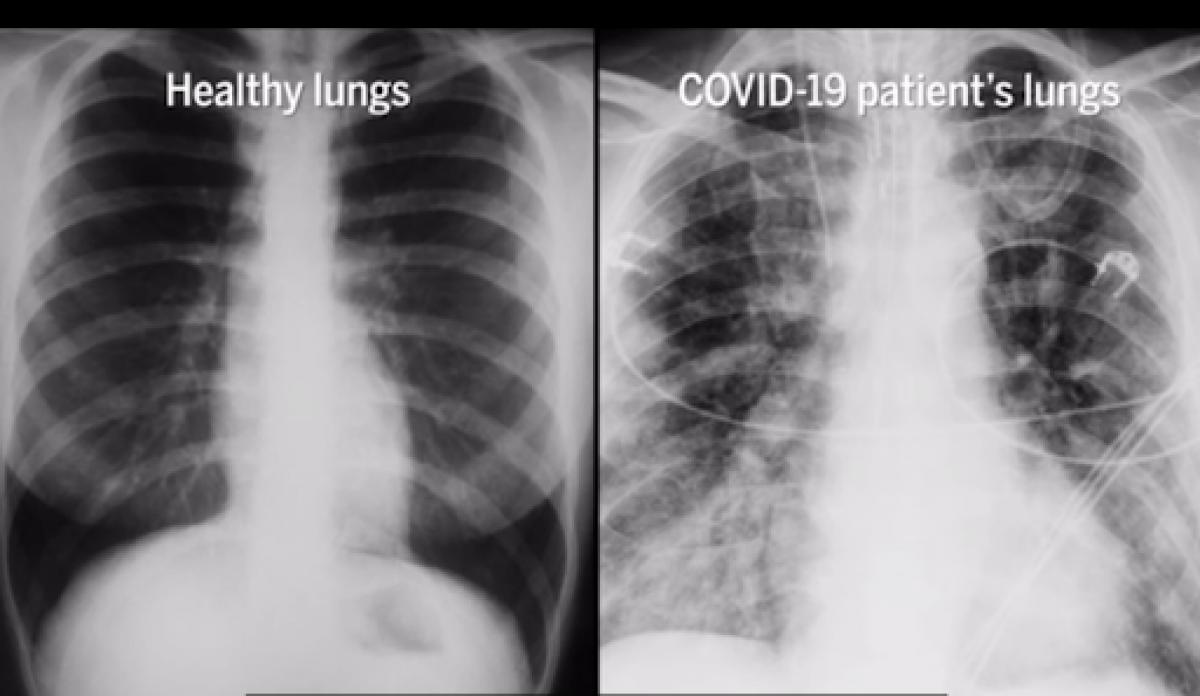

La lucha contra las secuelas del COVID-19 continúa, y ahora, la ciencia abre una nueva puerta hacia la recuperación funcional de los pulmones